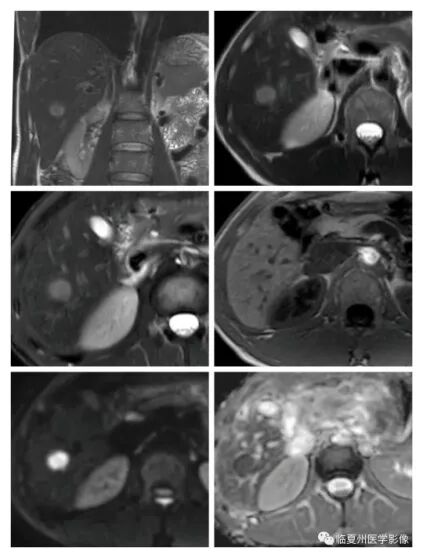

磁共振平扫

肝特异性造影剂检查后,肝脏结节定性诊断更加精准,使肝癌病灶无所遁形。